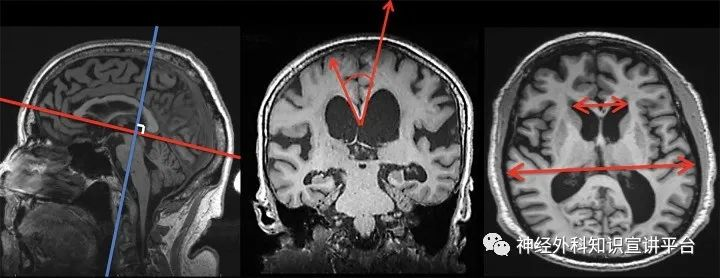

以上可以解释脑积水的一般情况,以下是几种特殊脑积水的发病机理:脑组织不是处处弹性一样,尤其在老年人中,脑组织的弹性大小不一的情况时有发生。这就导致脑室系统不均衡扩大,即DESH(Disproportionately enlarged subarachnoid space hydrocephalus,非对称性蛛网膜下腔脑积水),这一影像学特征是常压性脑积水特有表现。一般来说由于顶叶弹性较好,在一定压力差下可以发生移位,表现为脑室外膨,局部蛛网膜下腔受压,间隙消失,在冠状位上表现为CA(胼胝体角)小于90度;而其他脑组织弹性差的地方,相同的压力差不足以使脑组织发生位移,表现为脑室不外膨,局部蛛网膜下腔没有受压,间隙仍然存在。这种蛛网膜下腔的不对称性扩大就是DESH征。便于大家理解这一现象,可以引入两个概念:脑萎缩和脑压缩。顾名思义,前者是脑组织体积主动变小,多见于侧裂池、中脑环池周围的脑组织;后者是脑组织被动体积变小,多见于顶叶脑组织。当外界压力去除后,脑萎缩不会恢复,而脑压缩可以恢复之前的体积。这可以解释为什么常压性脑积水分流术后小便失禁和行走困难的缓解率明显高于痴呆的缓解率,因为前两者的中枢位于顶叶,而与痴呆密切相关的海马、杏仁核等边缘系统脑组织位于侧裂池、中脑环池周围。

获取DESH的标准扫描方法,CA小于90 度